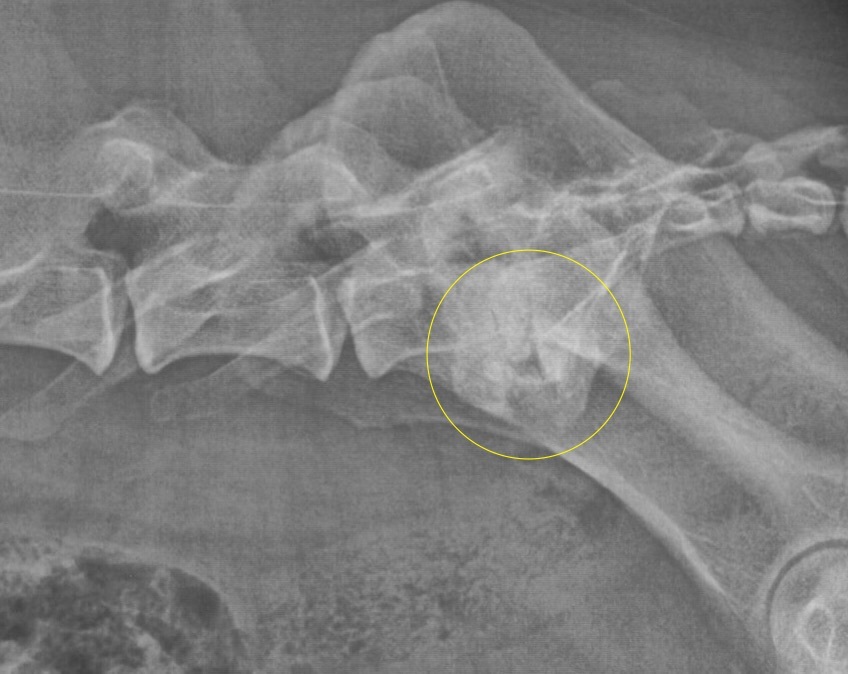

Nichts geht mehr? Urmels neue Menschen ergreifen den letzten Strohhalm. Ende April 2017 wird Urmel von ihrer Pflegerin Fatma nach Schweinfurt gefahren, um sie hier im Tiergesundheitszentrum näher zu untersuchen. Nach einer Gangbildanalyse (die bei einem so schwerfällig und nur mit Unterstützung einer Tragehilfe laufenden Hund natürlich nur eingeschränkt möglich ist) werden nach der anschließenden etwa zweistündigen orthopädischen Untersuchung aller Gelenke noch weitere Röntgenbilder von den Gelenken angefertigt, die in der Türkei nicht untersucht worden sind. Es zeigt sich, dass der Zustand noch schlechter ist als eh schon befürchtet: Urmel hat auch Arthrosen an der Wirbelsäule und weiteren Gelenken. Schließlich werden Urmel insgesamt 62 Berlock-Goldimplantate (das sind kleine spulenförmige Goldimplantate aus Dänemark) implantiert.

Infolge einer Gewichtsverlagerung bei solchen an einem Gelenk schwer gehandicapten Hunden kommt es über die Monate zu Folgeschäden an anderen Gelenken. Diese Schäden können sich bis zu den Zehengelenken ausdehnen. Häufig sehen wir dabei Arthrosen an den Zehengrundgelenken. Nicht selten sind die Sesambeine dieser Zehen frakturiert, durch Überlastung richtiggehend zerbröselt. Gerade solche Schäden aber werden leider zu oft übersehen. Wird eine solche Sesambeinfraktur übersehen, lahmt der Patient trotz aller weiteren Maßnahmen meist weiter. Da nutzt auch die beste Rekonstruktion der Patella am Knie nichts.